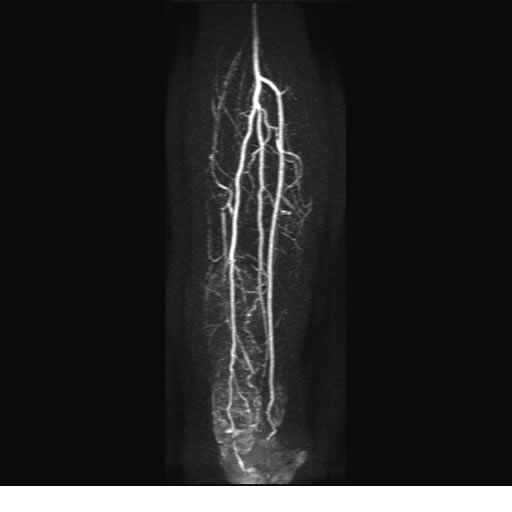

Se realiza estudio de MRI de pierna izquierda, utilizando secuencias Spin Echo y GRE en diferentes planos, se realiza angio MRI en fase arterial y venosa de pierna izquierda

El estudio demuestra masa a nivel de los músculos gemelos, más evidente en secuencia con pulso de saturación de grasa, en el estudio de angio resonancia de pierna la fase arterial no muestra ninguna anormalidad, en la fase venosa se observa acumulo del medio de contraste a este nivel.

Se concluye que se observa una masa de tejido muscular sumamente vascularizada compatible con un hemangioarcoma.